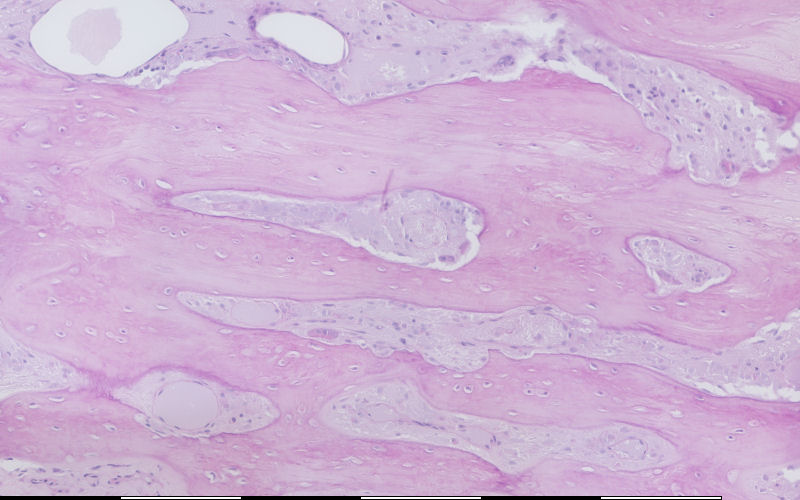

Bone-remodeling unit

Beenhermoduleringseenheid / Bone-remodeling unit Beenhermoduleringseenheid / Bone-remodeling unit Osteoklaste / Osteoclasts Howship lakunae / Howship's lacunae Oorblyfsel van Howship lakunae / Remains of Howship's lacunae Laag van osteoblaste / Layer of osteoblasts Snykonus: osteoklaste / Cutting cone: osteoclasts Vulkonus: osteoblaste / Filling cone: osteoblasts